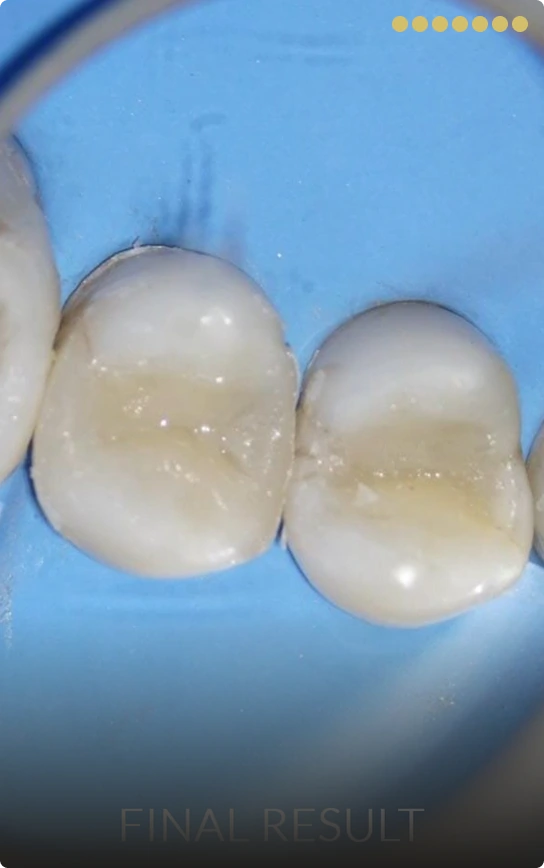

When a tooth requires more than a simple filling but less than a full crown, we provide biocompatible, aesthetic restorations that blend perfectly with your natural teeth.

Dental Inlay/Onlay

- In-house Custom-made inlay or onlay

- Preserves natural tooth structure